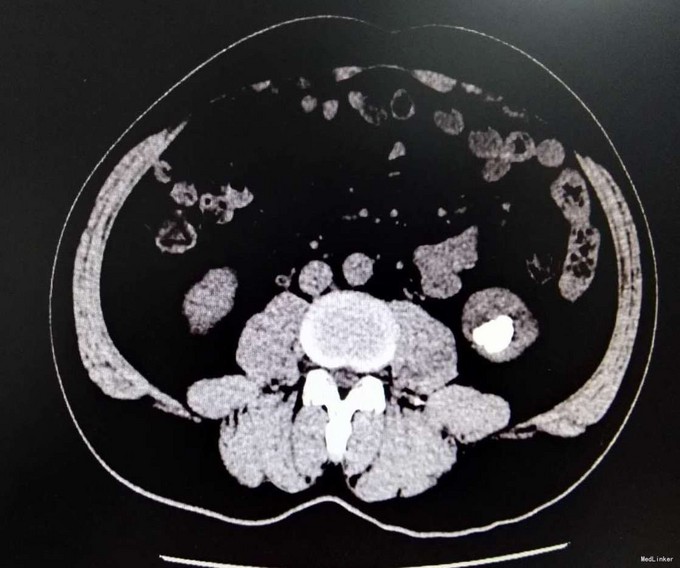

3、查体:未见明显阳性体征 4、辅助检查:外院平片:双肾多发结石;我院CTU:双肾多发结石,左侧肾盂输尿管连接处结石,并双肾积水,左肾明显,双侧肾盂、输尿管炎症。

5、诊断:肾结石(双肾多发结石) 6、治疗:入院后完善相关检查,双肾CTU:双肾多发结石,左侧肾盂输尿管连接处结石,并双肾积水,左肾明显,双侧肾盂、输尿管炎症。排除手术禁忌症后行左侧PCNL术,术后恢复良好,拔出肾造瘘管后,先出院休息,2周后返院进一步治疗